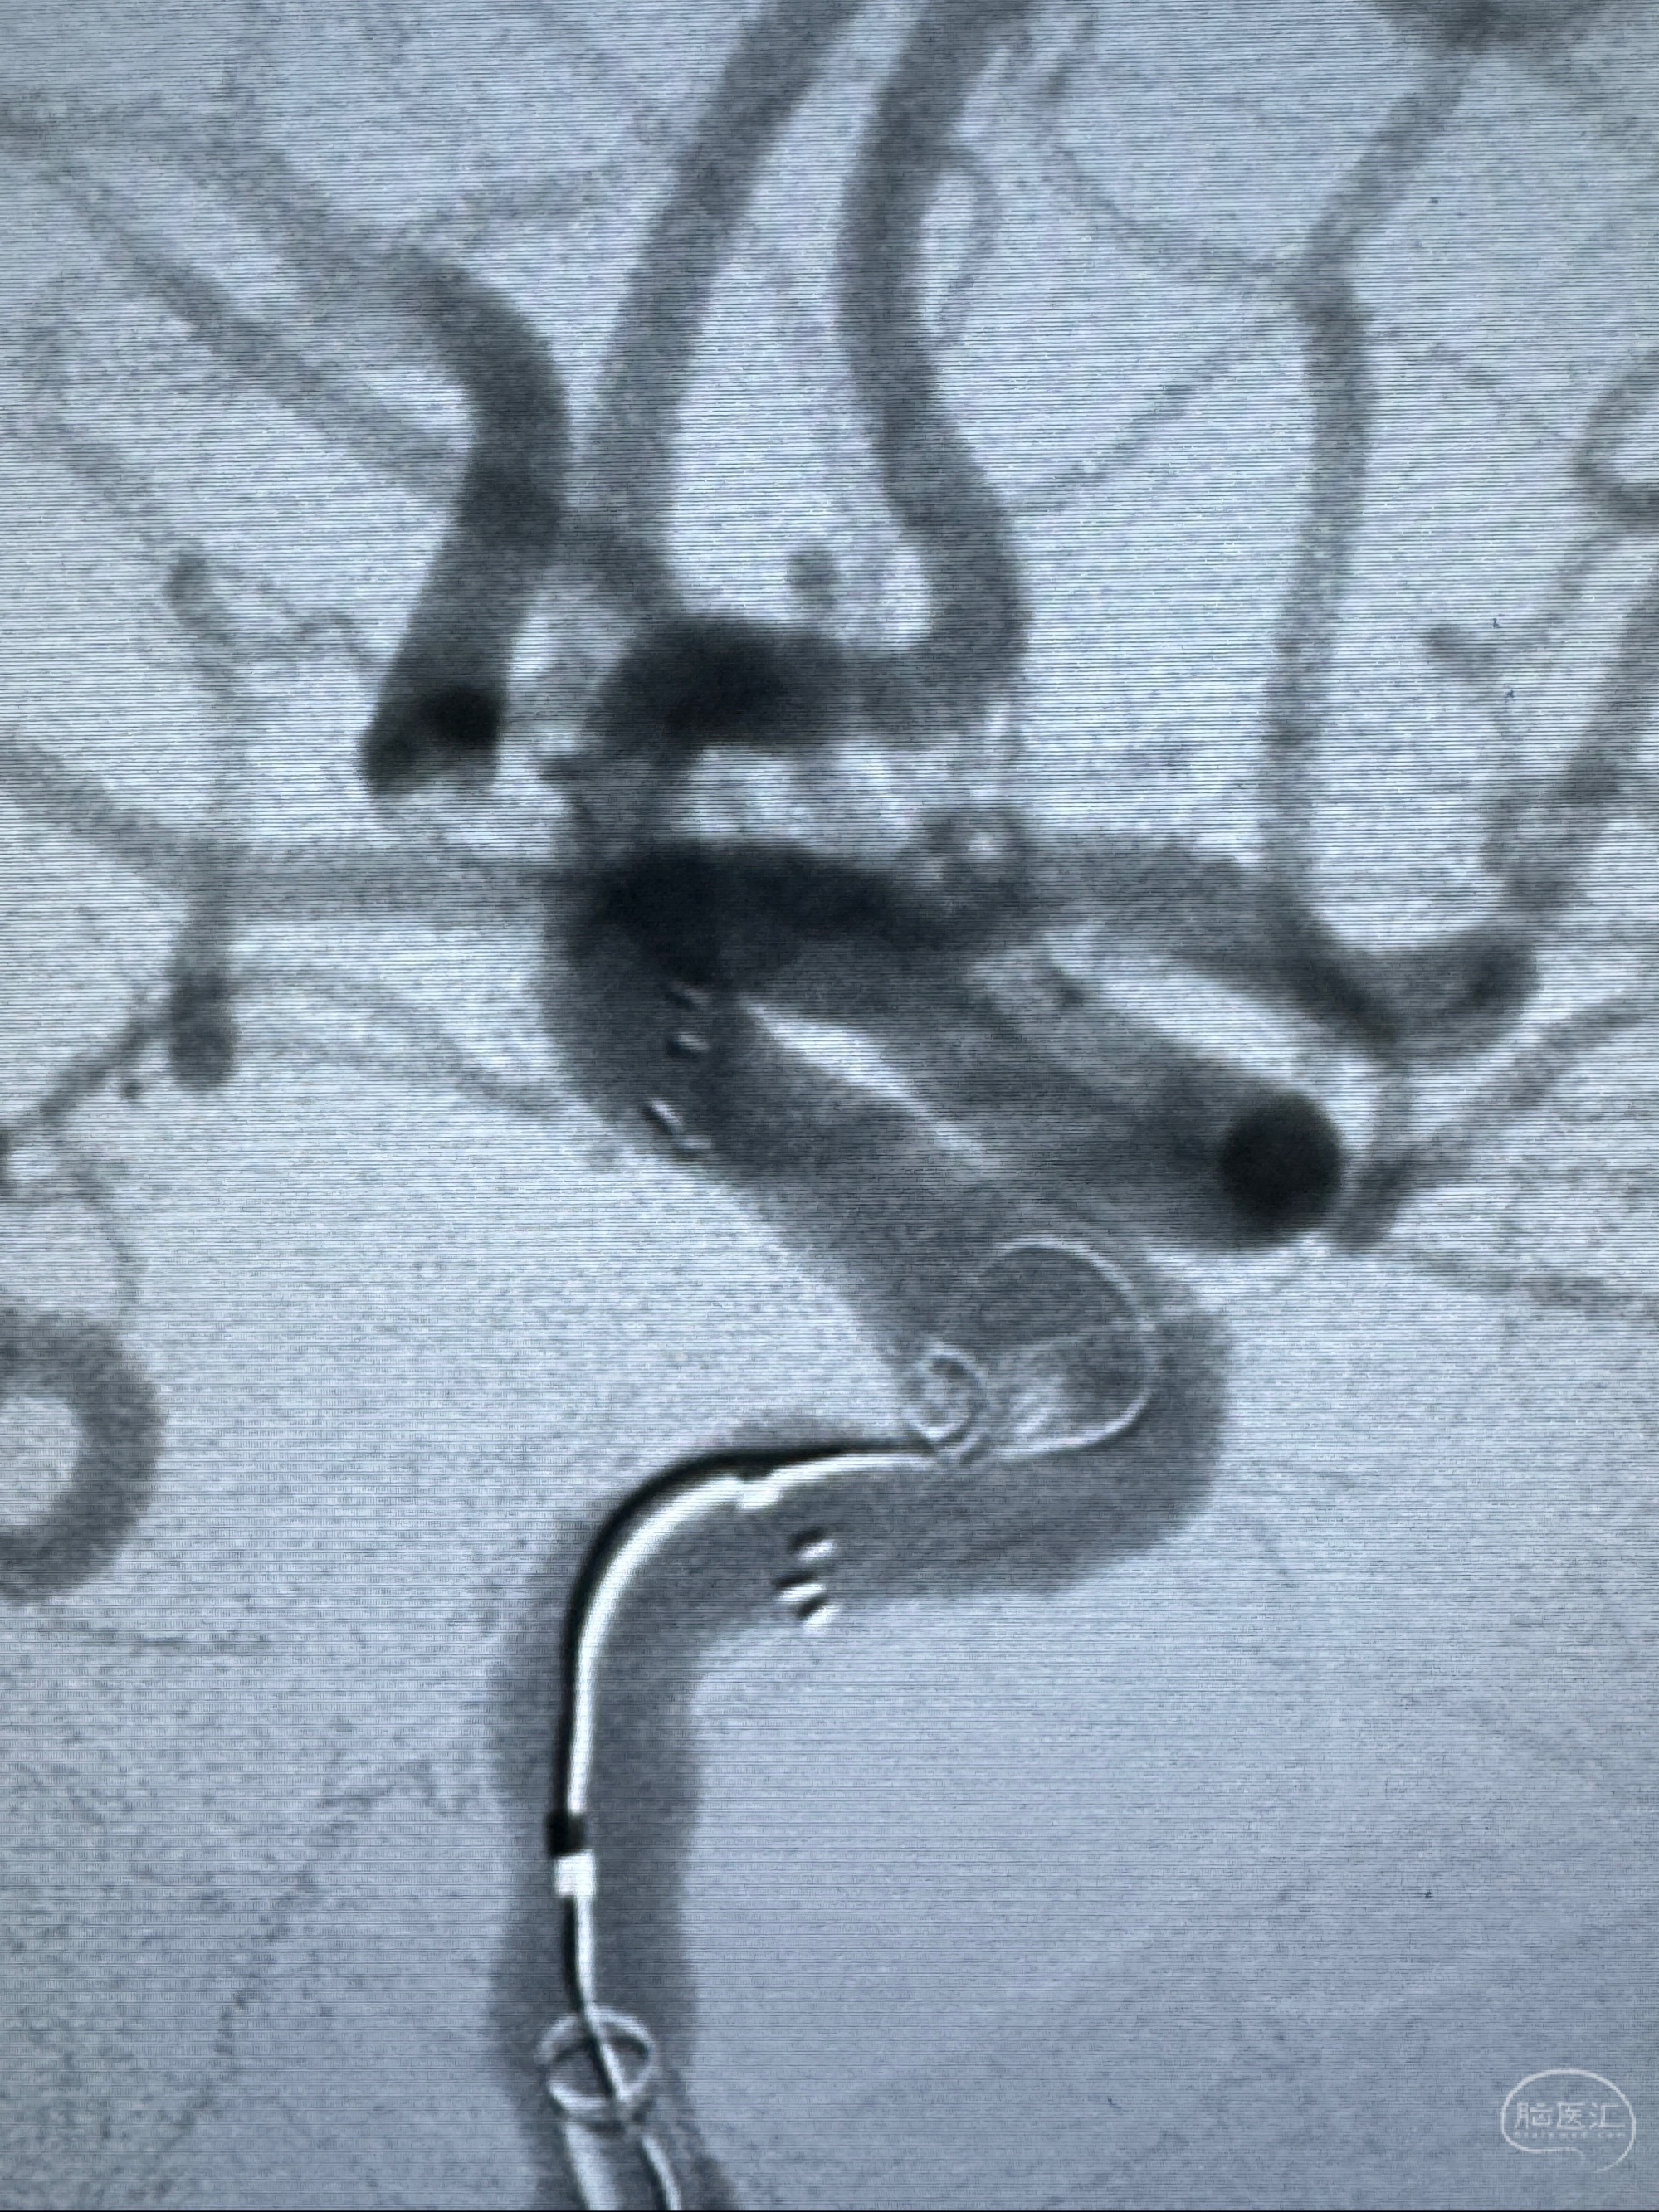

2023-11-13DSA:左侧颈内动脉眼动脉后壁动脉瘤

2023-11-29全麻下行NeuroformEZ4.5-20mm支架辅助栓塞